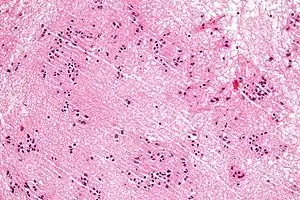

| Micrograph of a subependymoma showing the characteristic clustering of nuclei. H&E stain. | |

The diagnosis is based on tissue, e.g. a biopsy. Histologically subependymomas consistent of microcystic spaces and bland appearing cells without appreciable nuclear atypia or mitoses. The nuclei tend to form clusters.